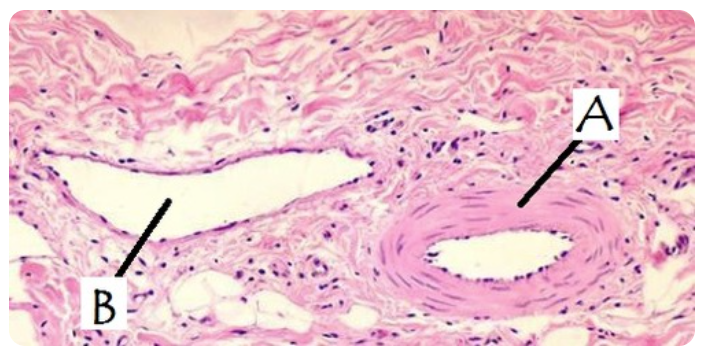

Blood Vessel A is a(n) _______ and blood vessel B is a(n) _______